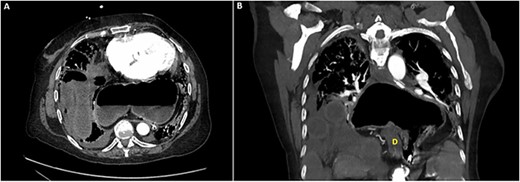

Abdominal radiography demonstrated a large hiatal hernia with intrathoracic stomach and concerns for gastric volvulus and partially imaged bowel gas within the right upper abdomen (Fig. 1). Computerized tomography of the chest and abdomen showed a large distended hiatal hernia with organoaxial rotation of the stomach, gastric distention with fluid and gas raising concern for partial obstruction. The right hemithorax contained multiple mildly dilated fluid-filled loops of small bowel with a prominent infiltrate of mesentery and decompressed bowel distally concerning for strangulation by a posterior lateral diaphragmatic hernia. There was no evidence of pneumatosis (Fig. 2).

Computed tomography of the chest and abdomen: (A) axial section demonstrating incarcerated small bowel within the right hemithorax as well as stomach within the posterior mediastinum. (B) Coronal section demonstrating incarcerated small bowel within the right hemithorax above the liver as well as hiatal hernia containing stomach in an organoaxial rotation as well as the duodenum (D).